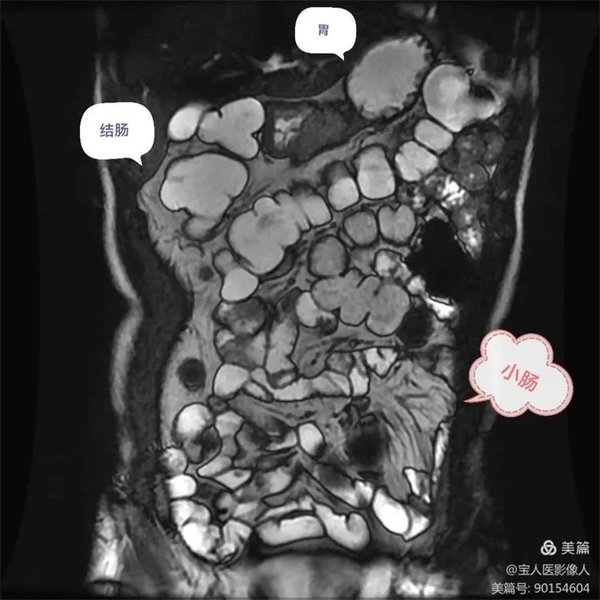

圖1,胃,小腸,結腸充盈顯示良好,局部小腸壁增厚,腸系膜病變組織包繞腸系膜動脈及分支血管塑形生長呈等T1,等T2信號腫塊。

圖6:胃,小腸充盈顯示良好,壁光滑,與周圍脂肪形成鮮明對比。